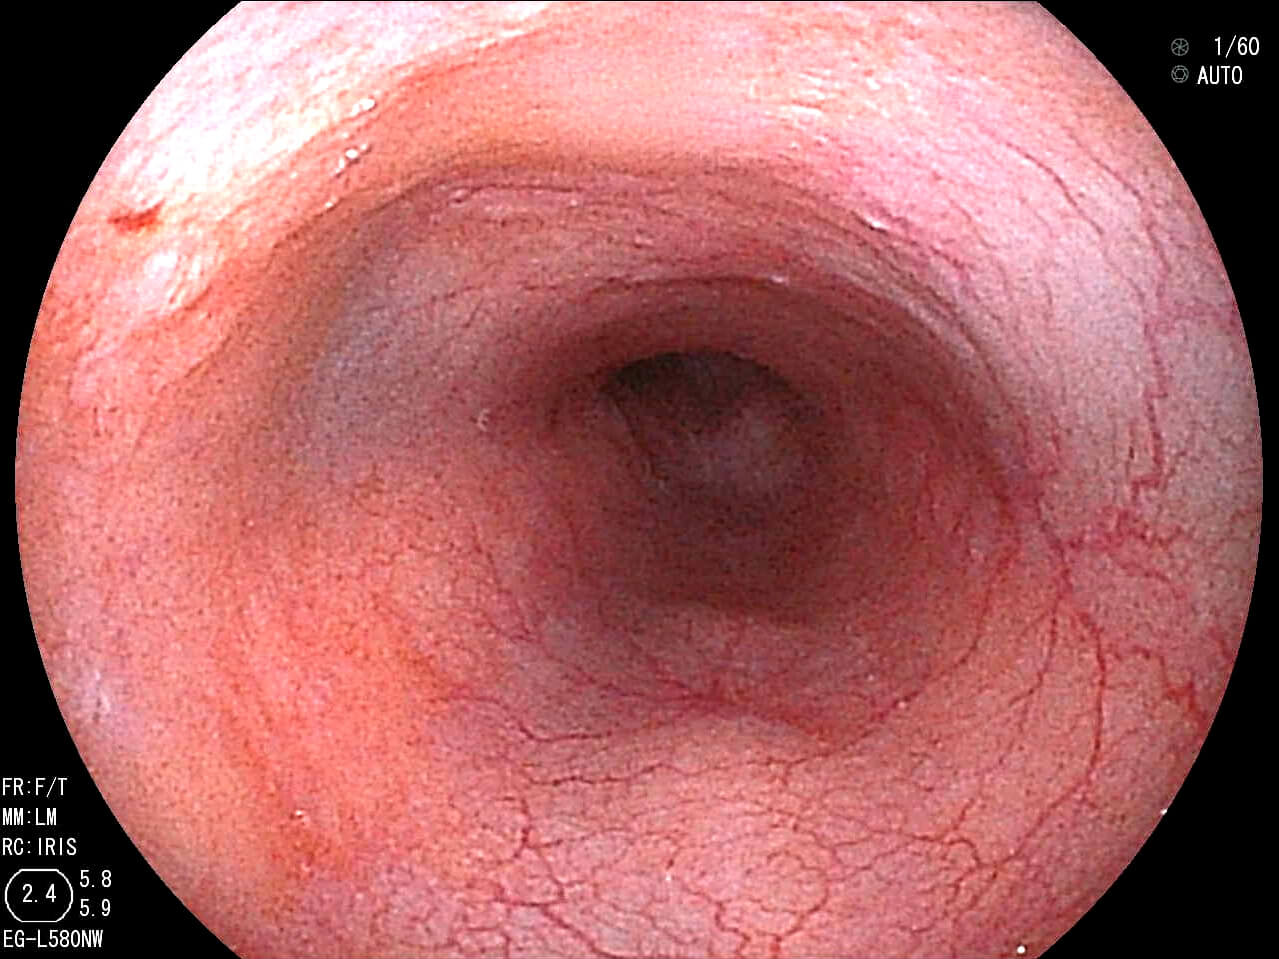

- Blue LASER Imaging (BLI)

- Blue LASER Imaging とは表面血管観察に適した短波長レーザー光を照射して得られる画像と白色光画像と画像処理することによって血管や表面構造の観察に適した画像を表示するものです。

と、難しい説明は置いておいて、実際の写真をみてみましょう。

上の写真は早期食道がんです。通常光の観察(左写真)(上写真)では癌の領域が不明瞭ですが、レーザー光源(右写真)(下写真)ですと、食道がんの領域が茶褐色となり、境界が一目瞭然です。このようにがんを早期で発見することにより、内視鏡で治療することが可能になります。